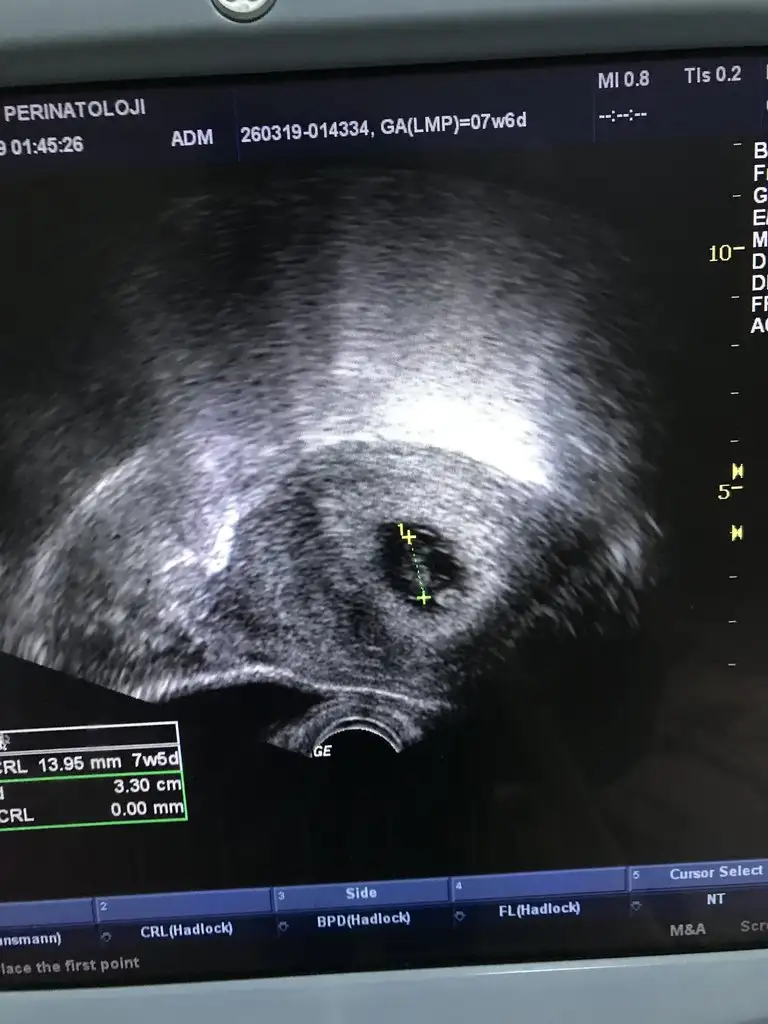

Evet bu sizin usg ise erkek bebeğiniz sanırım. Üşüme de varmış :)Ee bebek solda teoriye göre erkek ozaman

Haha :)O zaman bebeğiniz erkek olabilir :)

Senin kız sanırım canımBenimkinide yorumlayin ya :)

Bu arada rahimden bakıldı onu söylemeyi unuttumSenin kız sanırım canım

Rahimdense o zaman erkek gibi canımBu arada rahimden bakıldı onu söylemeyi unuttum